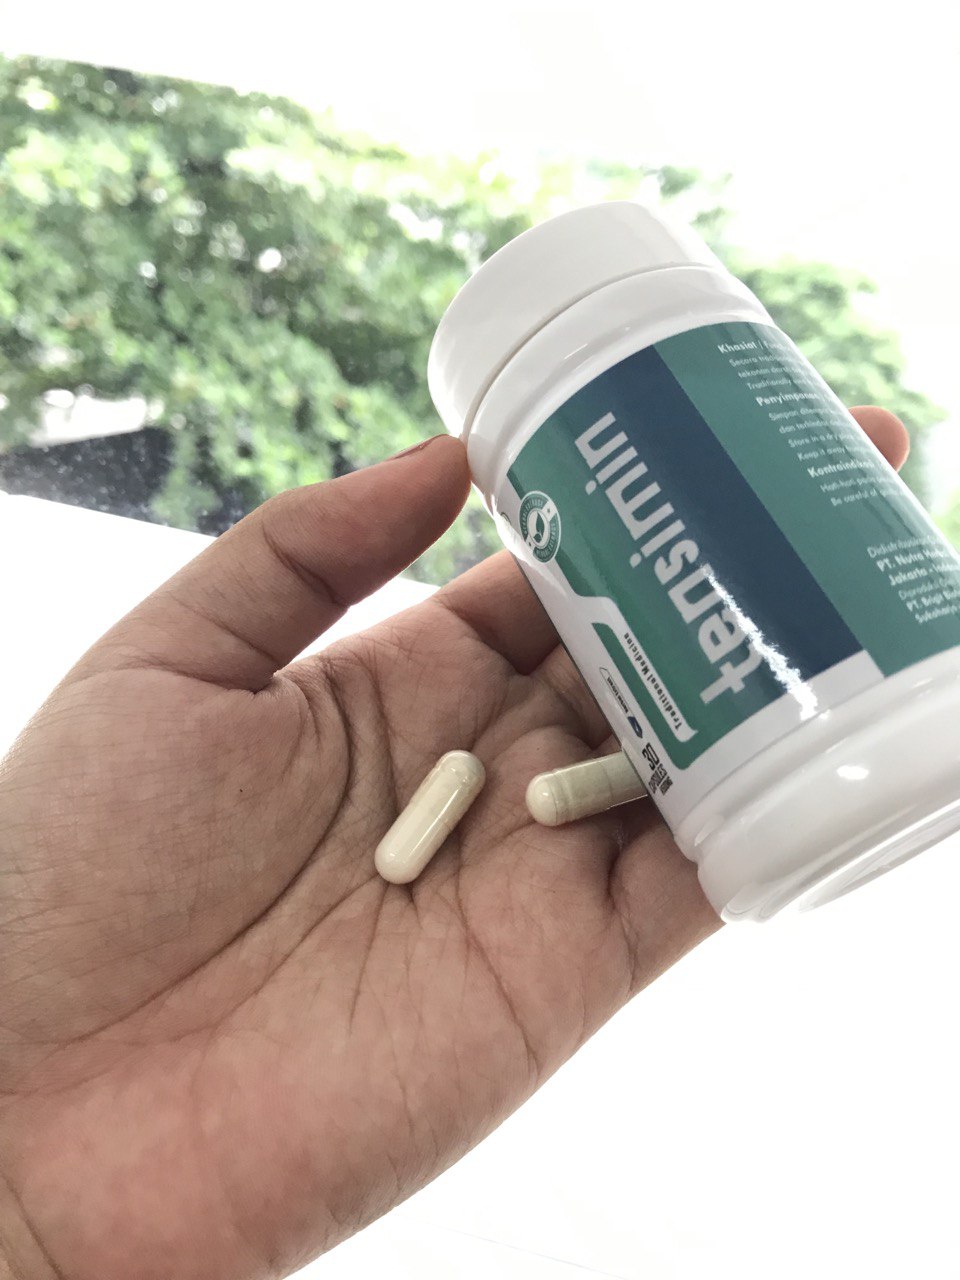

Tensimin adalah campuran kapsul ekstrak tumbuhan. Saat dicampur dengan air, senyawa-senyawa ini aktif. Agen-agen ini membantu membersihkan kolesterol, gumpalan darah (plak kalsium), dan sisa-sisa obat dari pembuluh darah, memastikan aliran darah yang lancar.

Bayangkan jika saya membeli Tensimin, membuka botol plastik yang menyenangkan, mengambil kapsul, dan menelannya dengan segelas air. Apa yang akan terjadi? Bagaimana cara kerja Tensimin?

Tensimin memiliki dua tujuan - menghilangkan residu kolesterol dari pembuluh darah dan merangsang metabolisme lemak yang tepat. Akibatnya, Anda mengalami peningkatan energi yang signifikan, keinginan untuk bergerak, mata yang cerah, dan semangat yang melonjak.

Tensimin bertindak seperti sayap kupu-kupu yang lembut, memulai rantai perubahan transformasional yang mengesankan. Dimulai dengan membersihkan pembuluh darah dari puing-puing yang terakumulasi selama beberapa dekade, Tensimin secara sistematis mengaktifkan proses peremajaan tubuh.